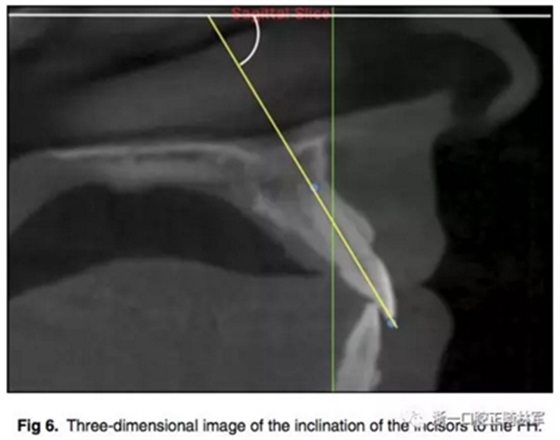

所有圖像導(dǎo)入Dolphin軟件中進行處理,2D側(cè)位圖像為使用Dolphin軟件使用相同的標準切割CBCT獲得。使用眶耳平面(FH)作為水平參考平面,使用垂直于眶耳平面(FH)同時通過A點的直線作為垂直參考平面。在上切牙最前點進行定點,牙根分界為自釉牙骨質(zhì)界至根尖,在牙根根尖、牙長1/2處、釉牙骨質(zhì)界下3mm處進行定點。使用FH的平行線測量頰側(cè)牙槽骨至牙根上3點的距離,同時測量A點與以上三條線段的距離,如圖所示。測量切牙的轉(zhuǎn)矩,使用通過切點、根尖的直線與FH平面的所成角。

根據(jù)每顆切牙相對上頜骨的位置在同一平行切面上各自確定A點,定好切牙最前點(MFMI),牙根長度依然為釉牙骨質(zhì)界至根尖點。使用與2D側(cè)位片上相同的方法進行牙根至骨皮質(zhì)的測量。轉(zhuǎn)矩的測量也同2D側(cè)位片。